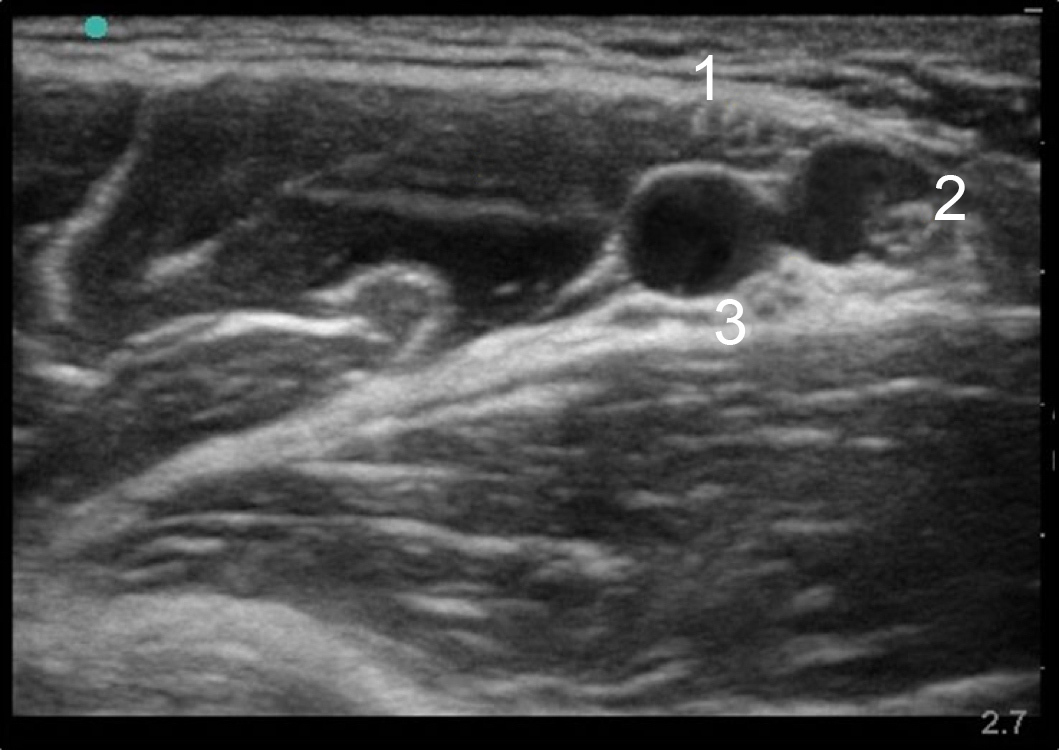

Image : Anatomie des nerfs axillaires

Nerf médian

Nerf cubital

Nerf radial